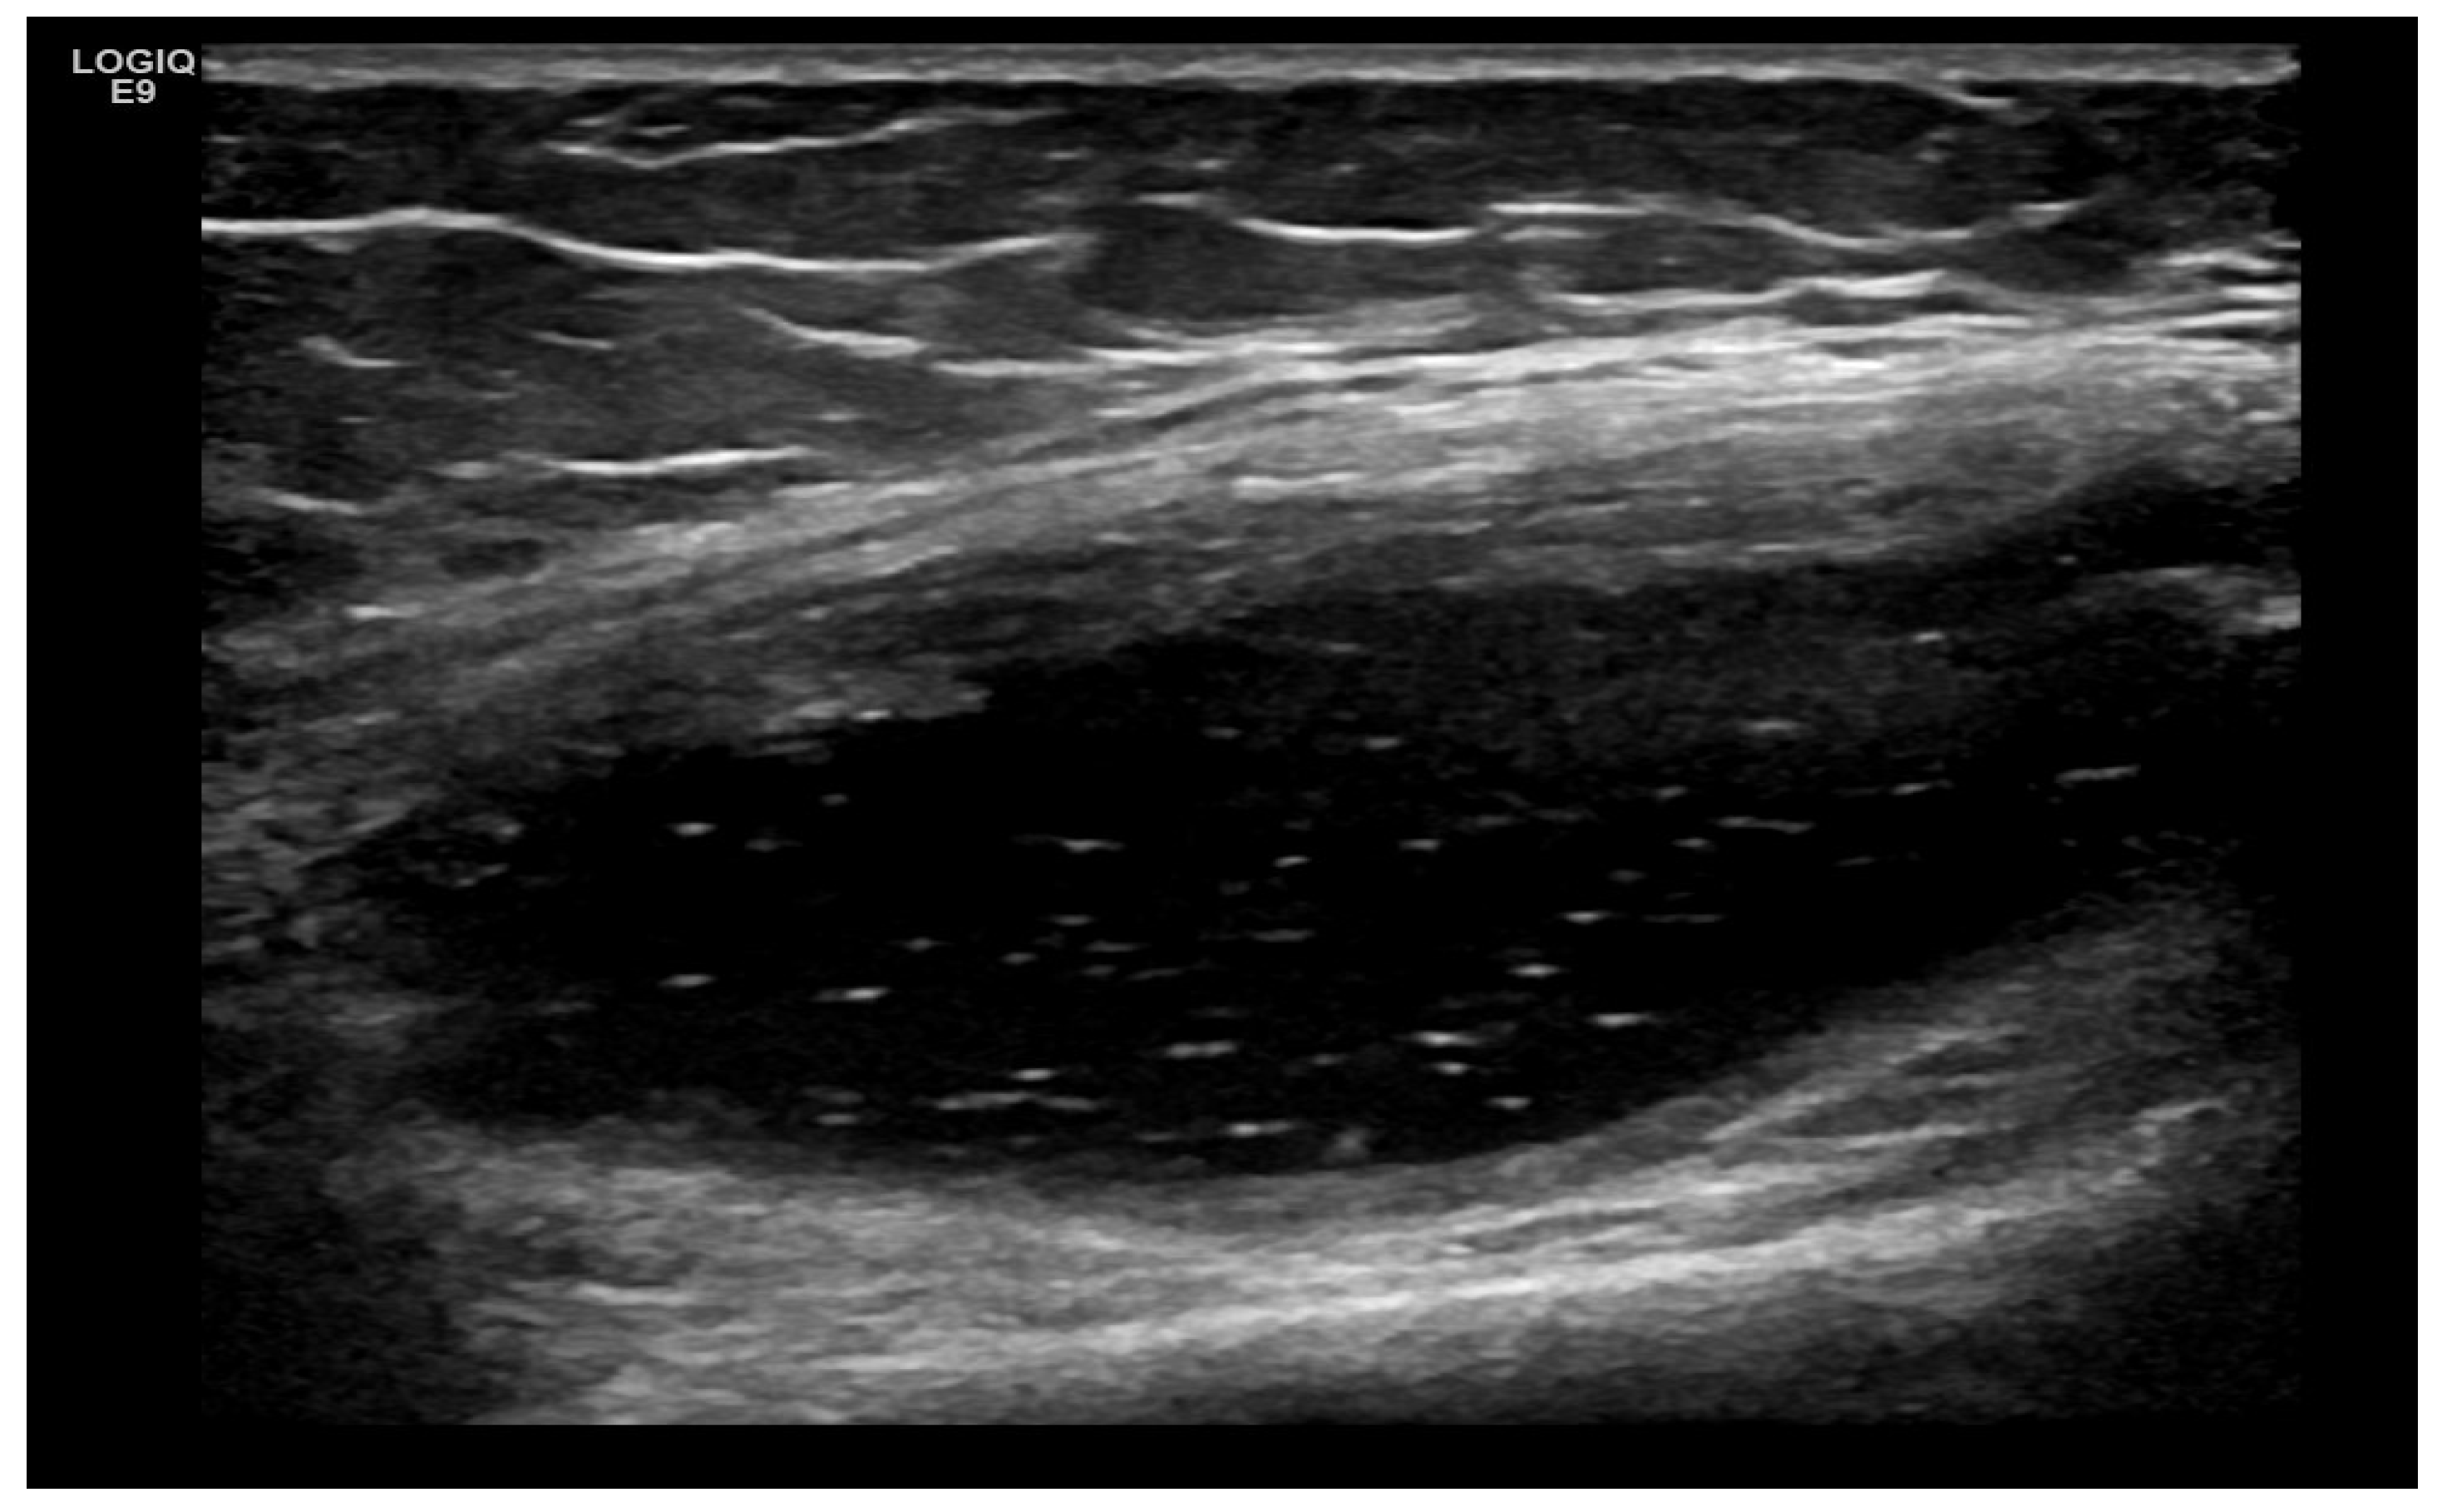

3. Suggestions for US Phenotypes

- Predominant intra-articular effusion (with minimal synovial proliferation (synovial sacs) and large intra-articular effusion;

4. Examples of US Phenotypes